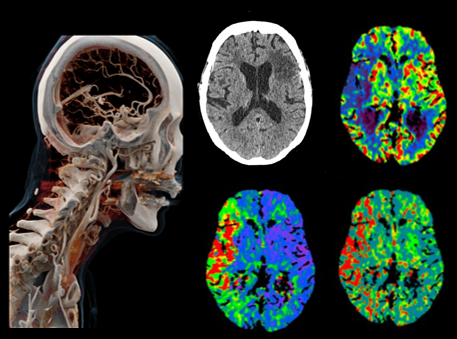

다음과 같은 검사가 가능합니다.

* 이해를 돕기 위한 이미지이며, 실제 촬영 시 이와 상이할 수 있습니다.